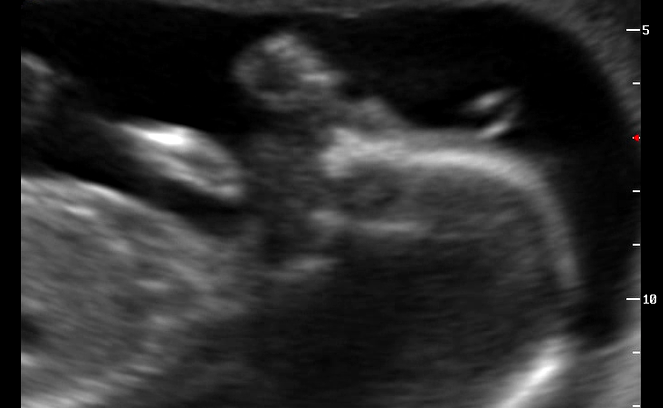

УЗИ, КТГ, доплервот и сходили мы с мужем на самое лучшее свидание) встретились с Чудом! и первое что он нам показал) пиписон, большой такой, "яркий" как выразился врач.

По измерениям мы день в день с акушерским сроком идем. Весим 397 гр в 20,4 недели.

Малыш очень активничал, поэтому сердечко толком замерить не удалось..сосуды убегали из под датчика. И СБ ну очень уж высокое 190 ударов в минуту....через неделю на контрольно узи сердечка ребенка и почек. Так как лоханка тоже слегка расширена...но и мочевой у него был полный, ну стеснялся он пИсать во время съемки)))).

ну и несколько фото: